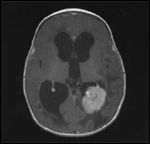

FIGURE 5

High-Grade Glioma

High-grade glioma including anaplastic astrocytoma (WHO grade III) and glioblastoma multiforme constitute about 14% of CNS tumors in children. These tumors can occur anywhere in the brain. In a recent Children's Cancer Group (CCG) study report of 131 evaluable children with high-grade glioma, over 90% of tumors occurred in a supratentorial location (63% in the superficial cerebral hemisphere and 38% in the deep or midline cerebrum) and only 8% occurred in the posterior fossa, including the brain stem and cerebellum (Figure 5).[53]